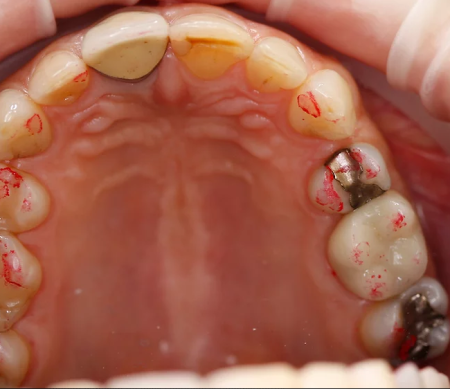

Окклюзионная бумага толщиной 40μ особенно хорошо подходит для двухцветной демонстрации статической и динамической окклюзии. Для этого на первом этапе окрашиваются в красный цвет все контактные пункты в положении центральной окклюзии, а затем проводится второй этап с окраской динамических контактных пунктов в синий цвет. Использование синей бумаги на первом этапе и красной бумаги на втором этапе также даёт хорошие результаты.